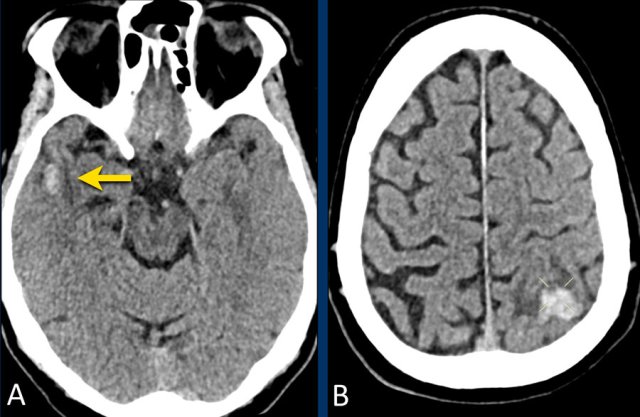

This patient presented with a subarachnoidal haemorrhage due to an aneurysm in the anterior communicating artery.

There is also an intraparenchymal heamatoma in the right gyrus rectus (arrow).

NCCT shows bilateral subarachnoid hemorrhage  and a parenchymal hemorrhage (yellow arrow).

CTA show at the location of the parenchymal hemorrhage a flow related aneurysm of the anterior communicans artery, which was considered the cause of the SAH.

Notice the hemorrhage next to the aneurysm (circle).

CTA also showed an AVM with the nidus in the left frontal lobe (green arrow).